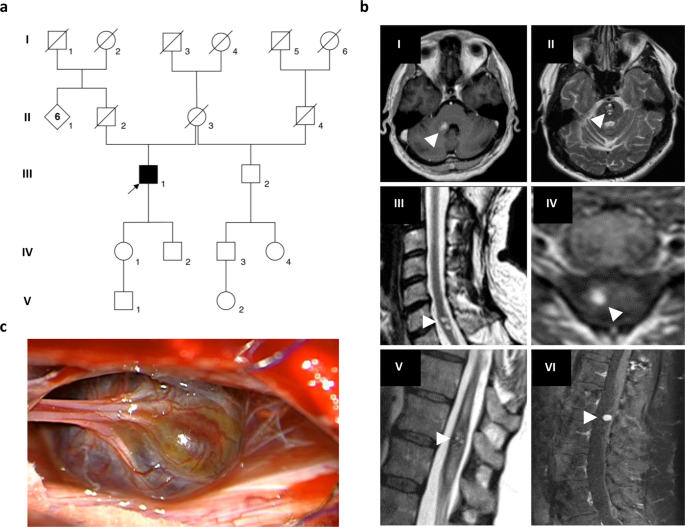

CCMs are benign vascular lesions that can occur anywhere in the brain parenchyma or leptomeninges but mainly occur in the supratentorial region. Conventional classification criterion is based on genetics and thus familial and sporadic forms can be distinguished.

Conventional classification criterion is based on genetics and thus familial and sporadic forms can be distinguished. However classification of sporadic cases with multiple lesions still remains uncertain. Cerebral cavernous malformations CCMs are collections of small blood vessels capillaries in the brain that are enlarged and irregular in structure.

Cerebral cavernous malformations CCMs are vascular lesions that can occur sporadically or as a consequence of inherited loss-of-function mutations predominantly in the genes CCM1 KRIT1 CCM2 MGC4607 OSM Malcavernin or CCM3 PDCD10 TFAR15. Cerebral Cavernous Malformation Panel. Is a 4 gene panel that includes assessment of non-coding variants.

When they contact the cortex they can represent a. Cerebral cavernous malformations CCMs are congenital vascular anomalies of the brain that can cause significant neurological disabilities including intractable seizures and hemorrhagic stroke. CCMs represent 5-15 of all cerebral vascular malformations and occur in 05 of the general population.